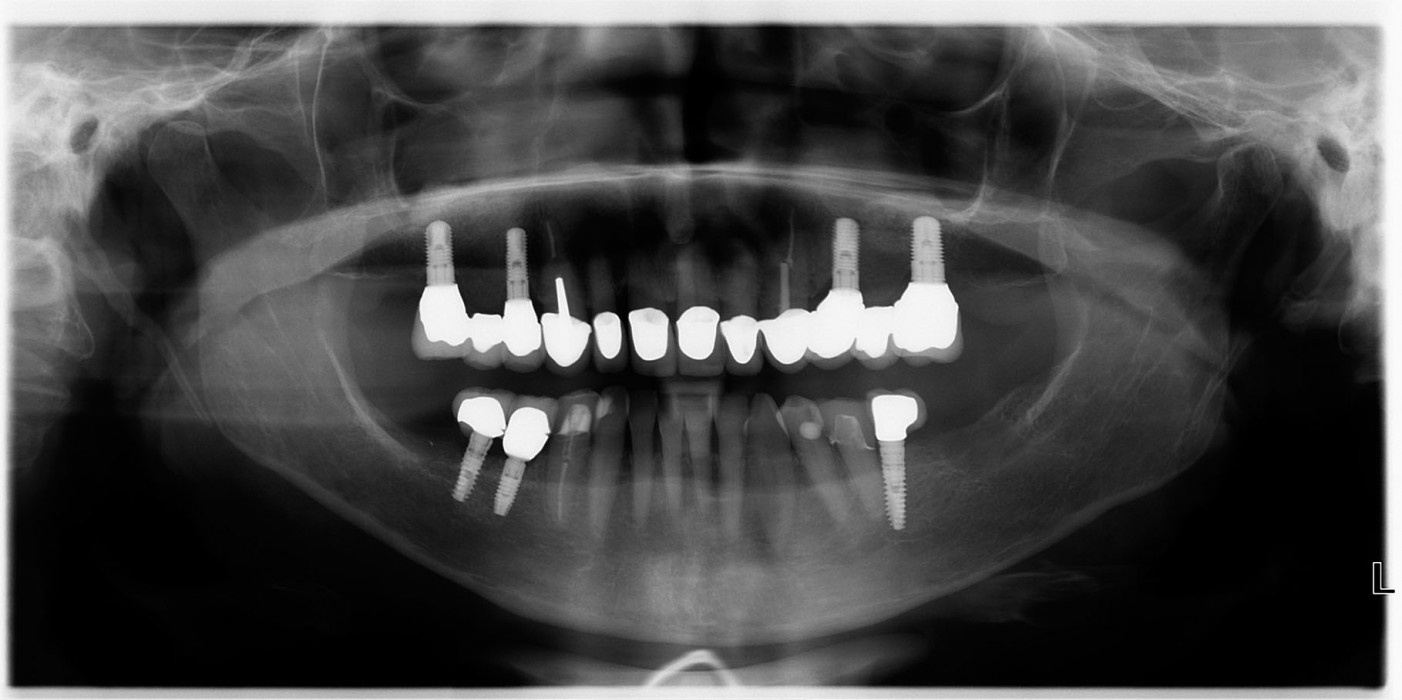

Die bisherige Versorgung, eine Teleskopprothese, stellte sich nach einer Tragedauer von etwa 18 Jahren als insuffizient dar. Als Vorbereitung erfolgte zur Reduktion der pathogenen bakteriellen Mundflora eine ausführliche Dentalhygiene. In der Folge stellten wir die Funktion der Prothese als Langzeit-Provisorium wieder her, indem wir den Zahn 13 endodontisch vorbehandelten, mit einem Stiftaufbau stabilisierten und die alte Krone repositionierten. Der mesiale und vestibuläre Kronenrand des Zahnes 17 wurden exkaviert und provisorisch mit Komposit verschlossen. Nach ausführlicher Beratung folgten wir dem Wunsch der Patientin nach festsitzendem Zahnersatz und entschlossen uns zu einer rein implantatgetragenen Neuversorgung mit dreigliedrigen Brücken. Aufgrund der verkürzten Zahnreihen im Unterkiefer entschied sich die Patientin gegen eine Vollbezahnung des Oberkiefers und einen Erhalt des Zahnes 17 über die Zeit des Provisoriums hinaus. Bereits das Orthopantomogramm der Ursprungssituation zeigte im ersten und zweiten Quadranten ein vermindertes Knochenangebot, was eine beidseitige Sinusbodenelevation unumgänglich machte (Abb. 1).

Nach sechs Monaten Einheilzeit erstellten wir ein Kontroll-OPG (Abb. 28), wurden die Implantate mittels Diodenlaser freigelegt und Sulcusformer eingebracht. Dadurch, dass wir vermeiden konnten, während des primären Augmentationseingriffes Narbenbildung im Bereich der keratinisierten Gingiva zu provozieren, blieb der Anteil der Attached Gingiva stabil. Die Abformung erfolgte eine Woche später. Alle Implantate wurden mit Zirkonoxidkeramik-Abutments (Simeda®) auf Reintitan-Klebebasen (Nemris®) versorgt. Die Gerüste der Brücken wurden mit der Sirona Cerec® 3MC XL-Schleifeinheit aus VITA In-Ceram® YZ-Blöcken der Größe 40/19 im CAD/CAM-Verfahren ausgefräst, gesintert und anschließend mit VITA VM®9-Keramik verblendet. Die Zähne 13 und 23 wurden mit Vollkeramik-Kronen versorgt. Der Zahn 17 konnte durch seine Vorschädigung und die außerordentlich lange Provisorientragezeit leider nicht erhalten werden. Die Kronen wurden mit Panavia® SA-Zement® (Kuraray®) definitiv eingegliedert (Abb. 29, 30).

Bei einer weiteren Implantation Regio 45 ergab sich die Gelegenheit einer Kontrolle des Resultates durch ein weiteres OPG nach etwa 1,5 Jahren Standzeit der definitiven Versorgung (Abb. 31). Hierbei zeigten sich stabile knöcherne Verhältnisse in beiden Augmentationsgebieten der Sinus maxillaris. Im radiologischen Vergleich lässt sich ein fortgeschrittener, wenn auch noch nicht vollständig abgeschlossener Umbau des Anteils an β-Trikalziumphosphat erkennen, während die Hydroxylapatitteile des easy-graft® 400 Crystal nach wie vor körnig imponieren. Klinisch zeigte sich die Brückenversorgung stabil und gut gepflegt mit anliegendem reizlosem Gingivalsaum (Abb. 32).